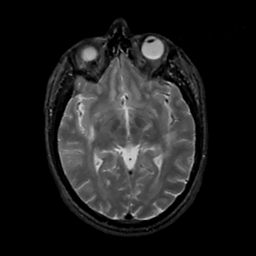

MR Study #1, February 10, 1991 -- Slice #23